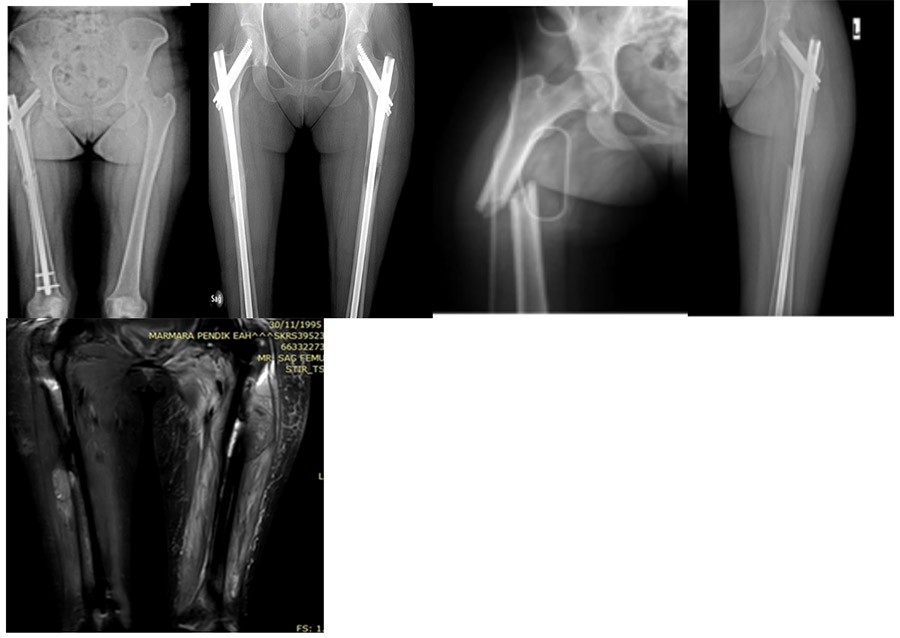

Before surgery: X-ray shows initial fracture in the right femur, right femur nail placement, risk of fracture in the left femur, recurrence in the left femur, and MRI shows a soft tissue recurrence component.